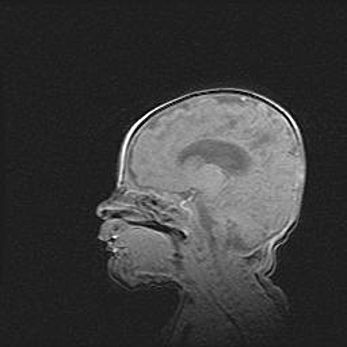

Аномалия Денди-Уокера. Признаки гипоплазии мозолистого тела.

Возраст: 5 месяцев 3 дня

Вес: 5550 г

Пол: мужской

Окружность головы: 39 см

Срок гестации: 40 недель

Аномалия Денди-Уокера – это порок развития головного мозга, для которого характерна триада симптомов: гипотрофия или аплазия червя мозжечка и/или полушарий мозжечка, расширение четвёртого желудочка с формированием ликворной кисты задней черепной ямки, гипертензионная гидроцефалия различной степени.

Гипоплазия мозолистого тела относится к дефектам внутриутробного этапа развития мозговой ткани, возникающим в процессе закладки структур головного мозга, что происходит на начальных этапах развития эмбриона.